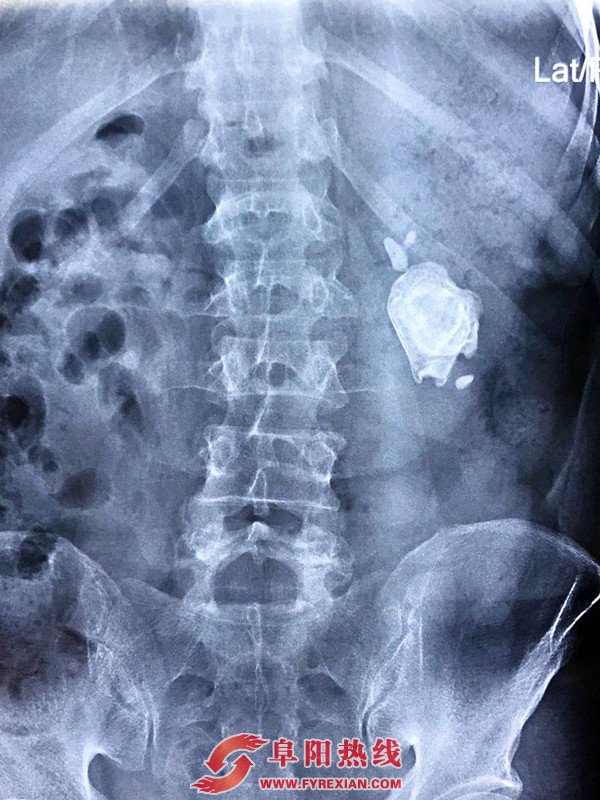

家住临泉县庙岔镇张庄村的张爱民自年前以来一直感觉腹部疼痛,近期,张先生自感疼痛加剧,于是在家人的陪伴下来到阜阳市人民医院泌尿外科就诊。经医学影像检查,张先生肾部有一状如鹅卵石的巨大结石,需住院进行手术治疗。如此巨大肾结石,对目前微创治疗是巨大挑战,一般选择开放性手术治疗,也就是老百姓所谓的“开大刀”。

经过手术前的认真准备,在征得患者及家属同意后,阜阳市人民医院于3月7日施行手术,在单卫民主任医师的全程关注下,手术由李明副主任医师主刀,袁振主治医师辅助,陈远哲住院医师,及规培医师戴志飞协助,在麻醉师任荣和台下护士郑培培、台上护士沈理想的共同配合下,仅用1小时余,就顺利完成了后腹腔镜下萎缩肾巨大肾结石肾实质切开取石术,术中几乎无出血,取出的肾结石大小如人们常见的鹅卵石一样,约5x4cm。